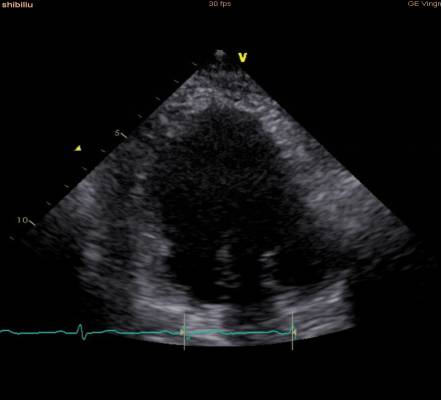

术前心超:

室间隔及心尖部收缩运动减弱;

心尖部室壁瘤形成;

左室舒张末期内径5.7cm,LVEF为35%;

轻度二尖瓣返流;

左房增大。